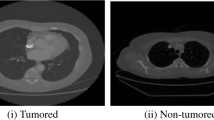

Lung disease is one of the most common illnesses that should be treated in its early stages to improve the chances that patients will survive. Making the cancer diagnosis is the radiologist’s most difficult task. The advantages of a sophisticated computer-aided system for radiologists are enormous. Numerous studies use ML algorithms to detect lung cancer. To predict lung cancer, a multistage classification is most frequently used. The segmentation and data improvement classification scheme has been completed. This study suggests a unique method for detecting lung cancer combining machine learning and quantum music photonics. Here, trumpet players’ data has been gathered and examined for noise reduction, normalization, and smoothing. With the help of support kernel vector Gaussian learning and spatio convolutional perceptron learning, the characteristics of the processed data are retrieved and categorized. Different lung cancer datasets are subjected to experimental study in terms of accuracy, precision, recall, AUC, TPR, and FPR. The efficiency of the suggested strategy for the identification and categorization of lung cancer nodules is demonstrated by experimental data. The proposed technique attained accuracy of 97%, precision of 94%, recall of 85%, AUC of 72%, TPR of 55%, FPR of 45%.